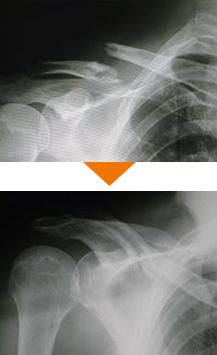

スポーツ外傷

スポーツ外傷、交通外傷、労働災害、家庭や職場による一般外傷などは認定医が適切な診断、診察を行います。